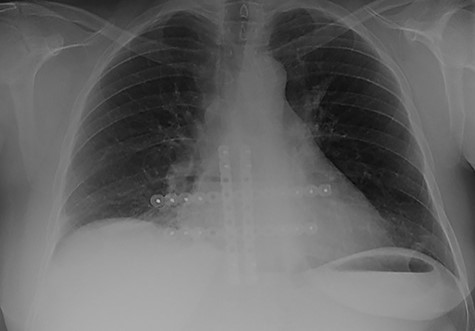

The first case at our institution was a 39-year-old woman who had a history of left breast carcinoma treated with left mastectomy, axillary node clearance and immediate reconstruction under the care of the breast team 3 years prior to presentation. She had no significant co-morbidities. Her past surgical history consisted of the aforementioned oncological operation, appendicectomy and cholecystectomy. She had completed adjuvant oncological therapy in the form of chemoradiotherapy and maintenance hormonal therapy. Her post-operative histology was consistent with a fully excised left breast ductal carcinoma and spread to three out of nine lymph nodes. Due to positive oestrogen receptor-2 status, she had been placed on hormonal therapy. She re-presented with chest wall and sternal pain and subsequent computer tomography (CT) imaging demonstrated a suspicious looking lytic lesion in the mid-sternum (Fig. 1). She underwent a biopsy of this lesion, which confirmed the diagnosis. She had been taking opioid medication for the pain. She was seen in clinic and counselled for partial sternectomy and reconstruction. She underwent partial sternectomy and underwent reconstruction with vertical and horizontal Synthes® plates. Her post-operative recovery was unremarkable. Post-operative histology was consistent with metastatic breast carcinoma completely excised. The recovery was uncomplicated and the patient was seen in clinic with a satisfactory chest radiograph demonstrating the sternal Synthes® plates (Fig. 2).